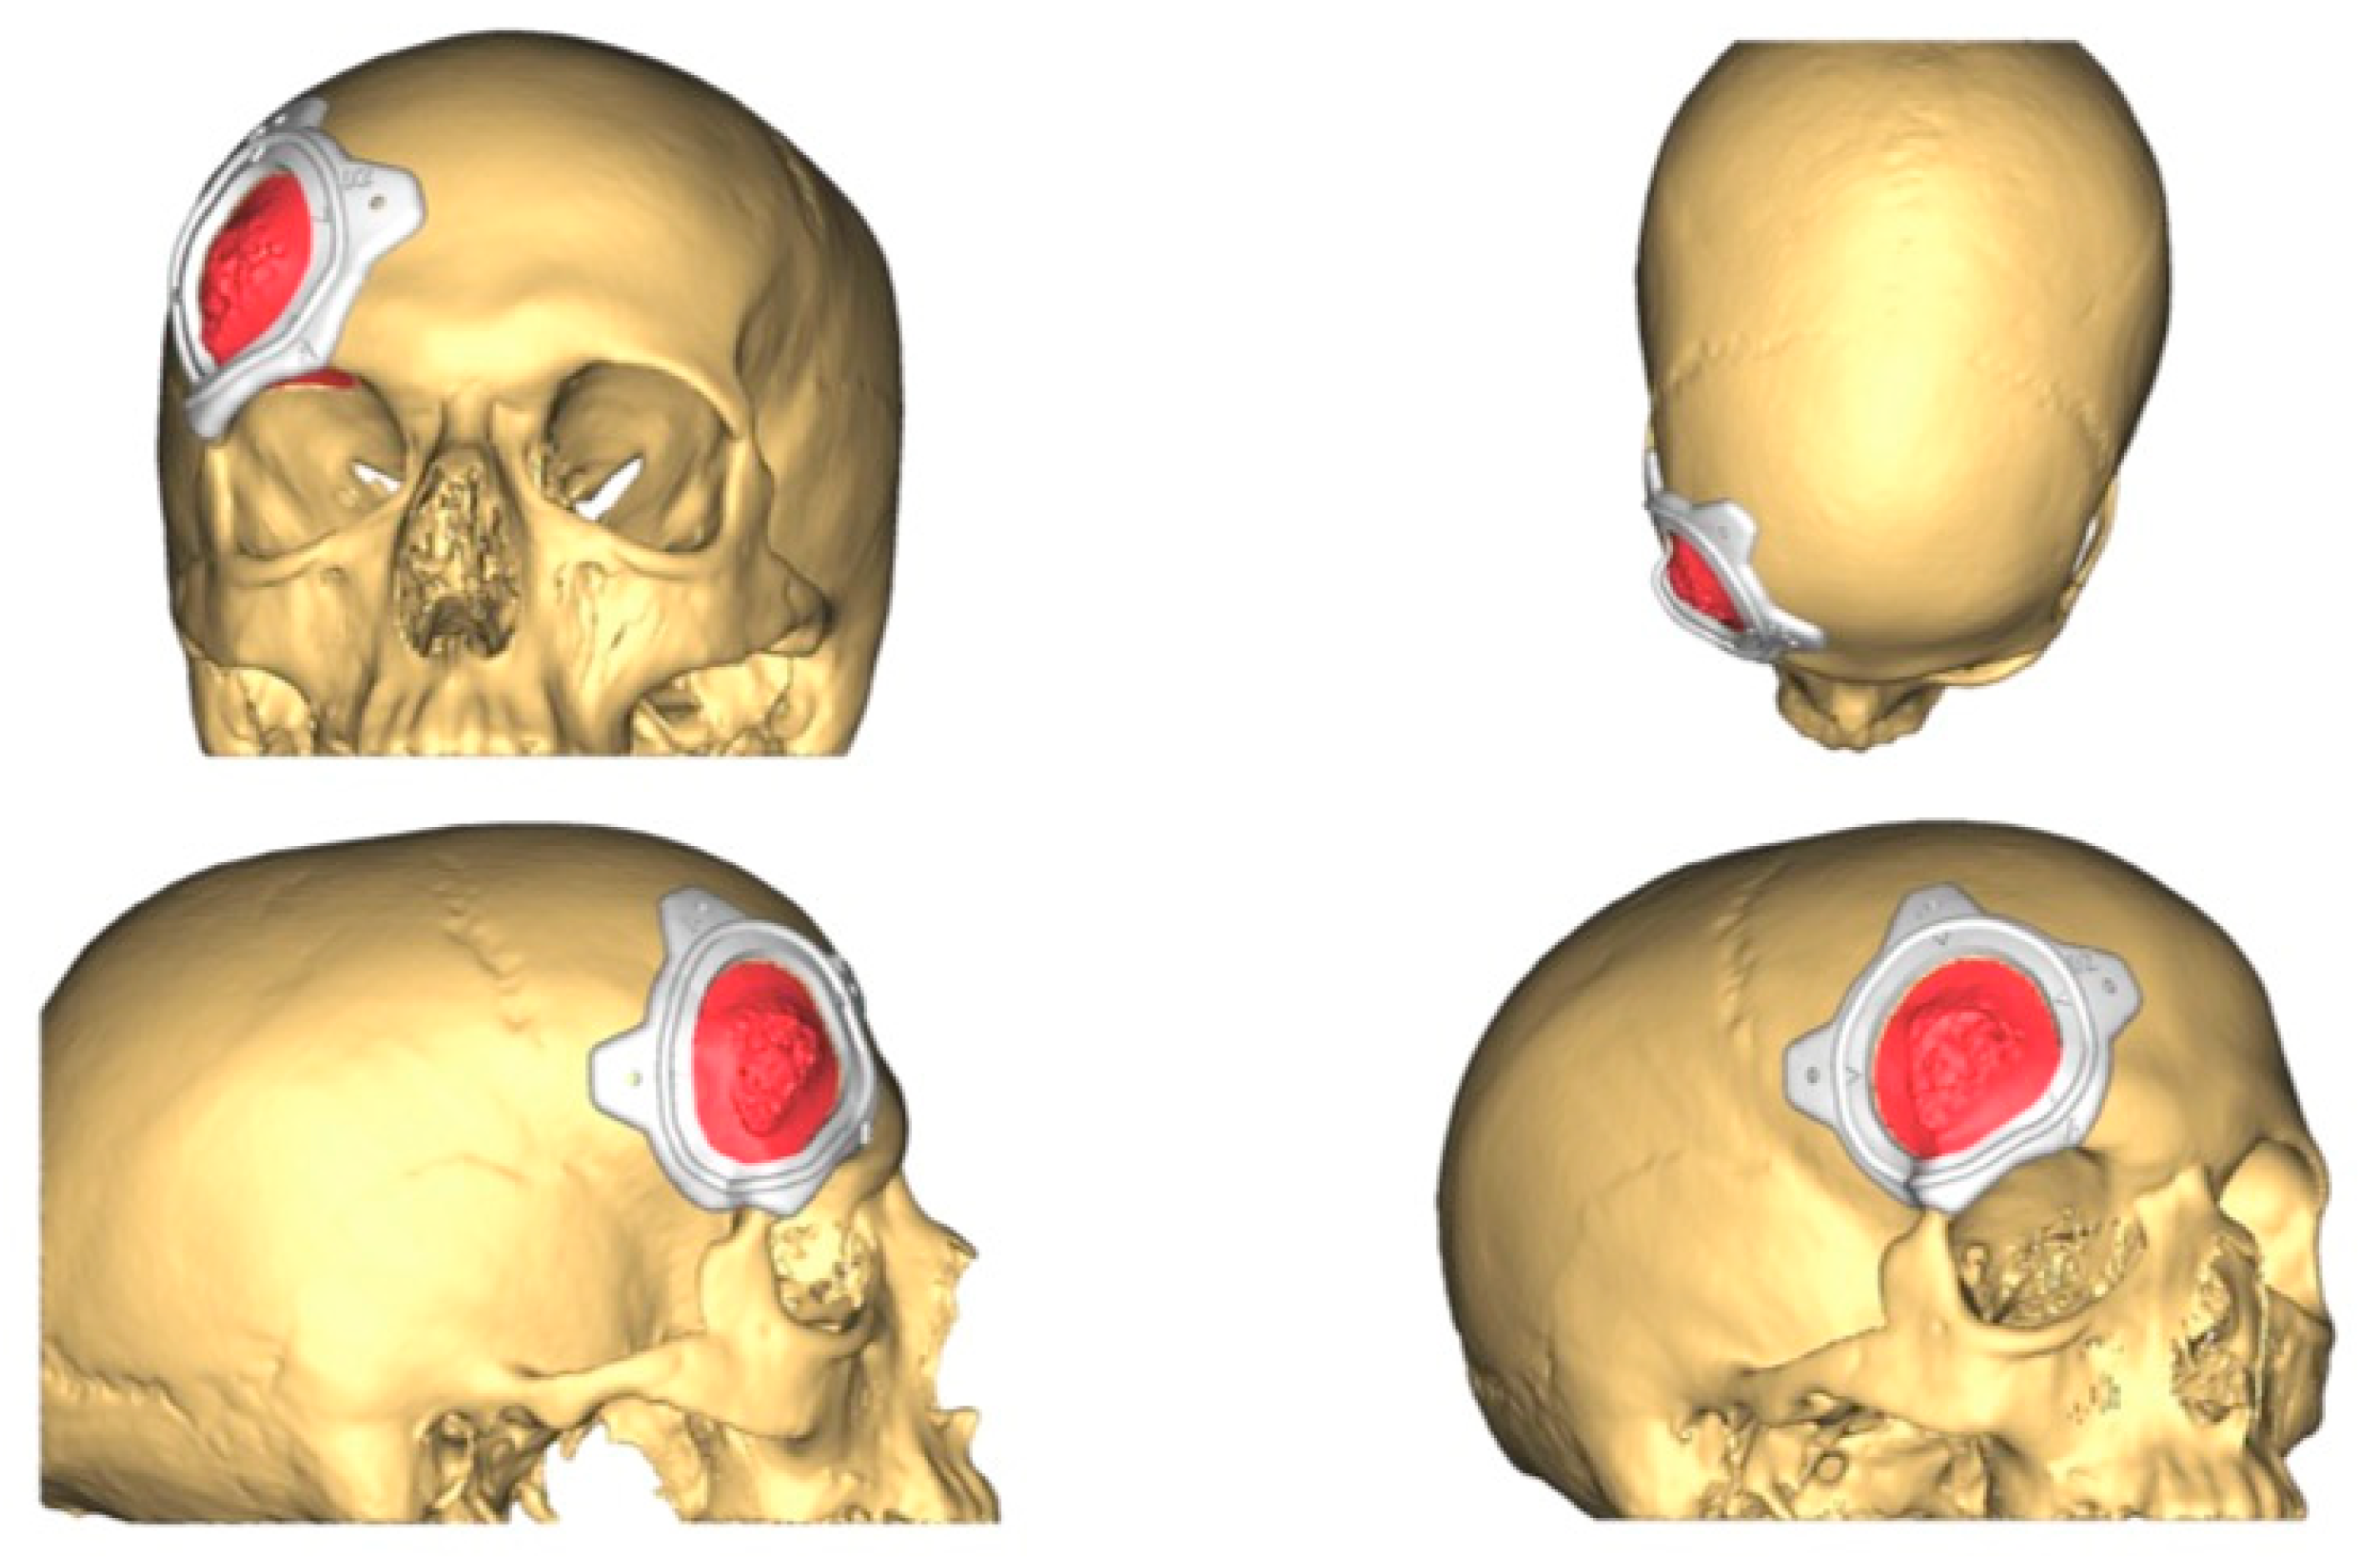

2.3.2. CAD-CAM Design of the PEEK Prosthesis

| 1 | 53/F | L/25 mm | Y | 4 mo | Dystopia | N | CT, MRI | Supraorbital rim, orbital roof | Intraosseous venous malformation | - | Resection + reconstruction | Y | Y | 1st, 2nd, 3rd | Coronal | Y | Piezoelectric device | N | PEEK prosthesis | 7 y/N |

| 2 | 54/F | R/33 mm | Y | 9 y | N | Y | CT, MRI | Frontal bone, orbital roof | Intraosseous venous malformation | - | Resection + reconstruction | Y | Y | 1st, 2nd, 3rd | Coronal | Y | Piezoelectric device | N | PEEK prosthesis | 6 y/N |